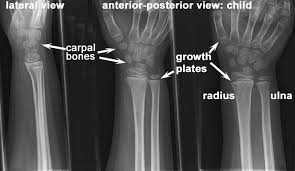

Normal Wrist Joint Child Radius And Ulna X Ray Becoming A Doctor